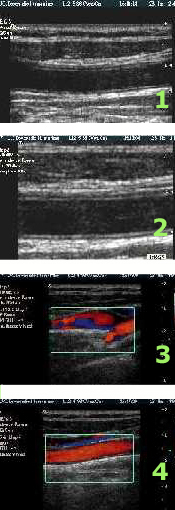

– Ecodoppler vascolare: studio delle vene e delle arterie.